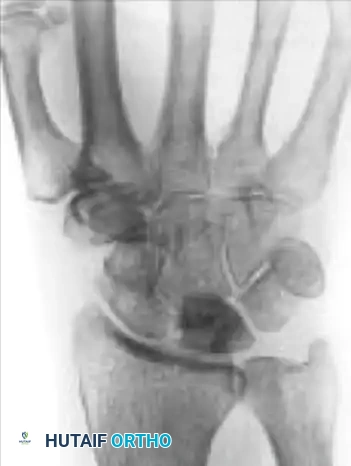

Fractures of the lunate are notoriously difficult to detect on standard posteroanterior (PA) and lateral plain radiographs due to the superimposition of the radial styloid, scaphoid, and triquetrum.

- Advanced Imaging: Thin-slice computed tomography (CT) or complex motion tomography is frequently required to definitively identify and characterize the fracture pattern.

- Fracture Patterns: Lunate fractures may present as nondisplaced, displaced with large fragments, avulsed (especially at the dorsal pole where critical radiocarpal ligaments attach), or highly comminuted.